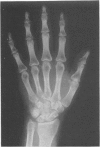

Images in this article